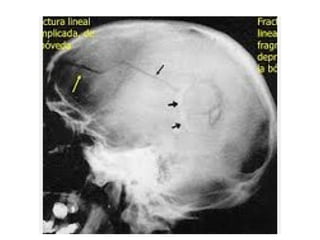

Trauma craneoencefálico:

Fractura de cráneo.

• Lineal.

• Deprimida.

• Conminuta.

• Diastasada.

Fractura